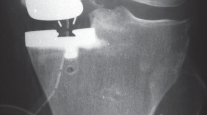

1. التخطيط قبل الجراحة

-

القوالب المسبقة (Preoperative Templating):

يتم استخدام الأشعة السينية لتحديد حجم وموضع المكونات المزروعة بدقة قبل الجراحة.

التصوير الطبي ضروري لتأكيد التشخيص وتحديد مدى تلف المفصل:

-

الأشعة السينية العادية (Plain Radiographs):

- المنظر الأمامي الخلفي (AP): يُظهر الركبة من الأمام.

- المنظر الجانبي (Lateral): يُظهر الركبة من الجانب.

- المنظر الخلفي الأمامي المثني (PA Flexed): يسمح بتقييم أفضل للجزء الخلفي من الركبة وقد يكشف عن تغيرات أكبر في الحجرة الخلفية الوحشية.

- منظر شروق الشمس (Sunrise/Patellofemoral): لتقييم المفصل الرضفي الفخذي.

- الأشعة السينية الطويلة للطرف السفلي بالكامل (Full-length standing radiographs): من الورك إلى الكاحل، وهي مفيدة جدًا، خاصة إذا تم استخدام تقنيات الملاحة الحاسوبية. تُظهر هذه الأشعة المحاذاة الكلية للطرف السفلي.